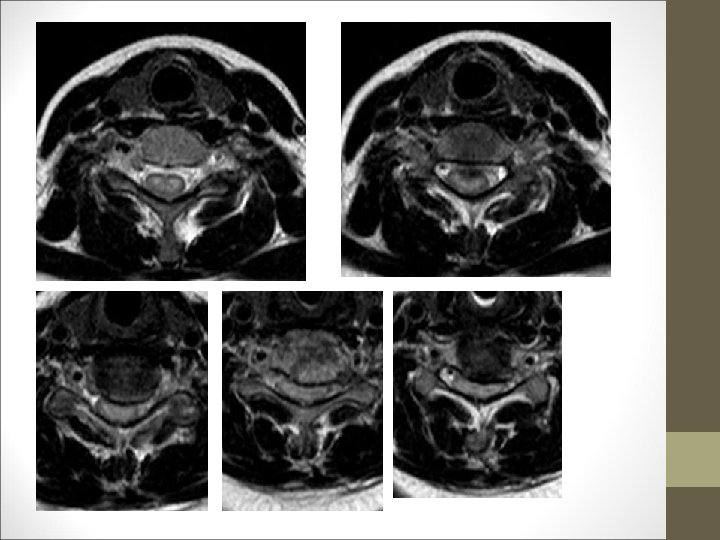

TC Desplazamientos de fragmentos óseos ¿Algo mas? Desplazamientos discales y lesiones ligamentosa FACULTAD DE MEDICINA DEPARTAMENTO DE CIRUGÍA NEUROCIRUGÍA RM